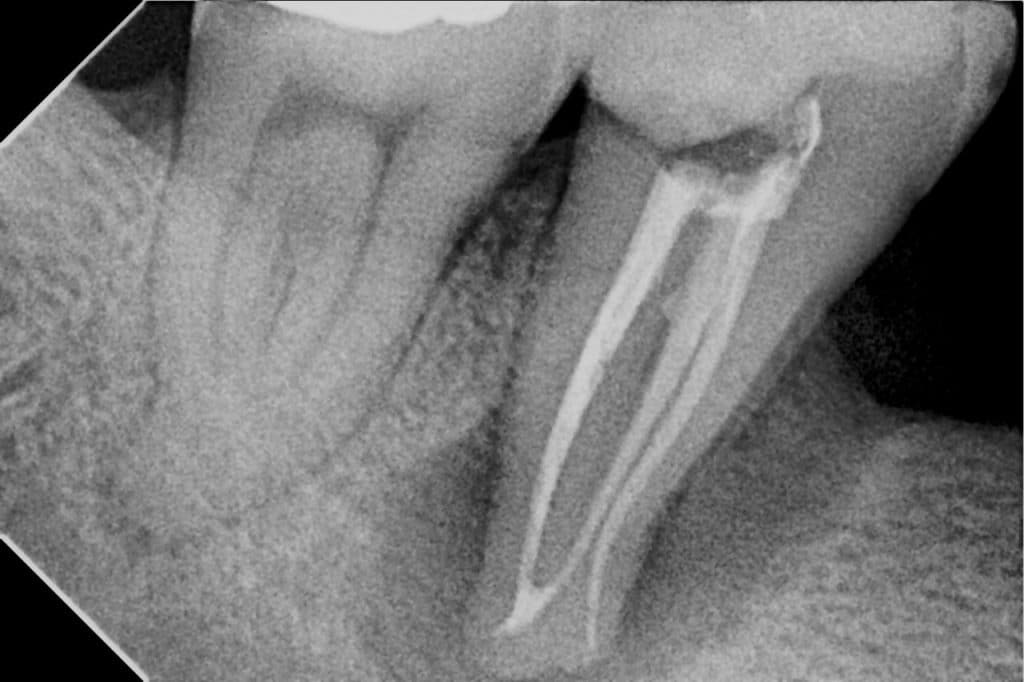

Cones fit

Obturation